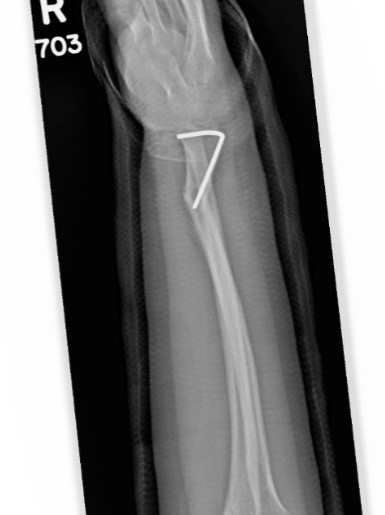

Загальна рентгенографія

Спеціальні можливості для рентгенографії: